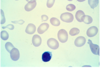

47

Plasmodium vivax

48

babesia